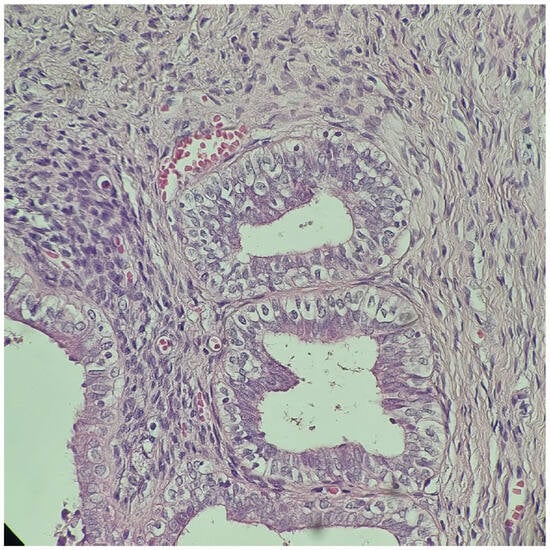

Figure 2.

Rudimentary uterus with hypoplastic endometrial and myometrial layers. H&E stain, 400×.

After orchidopexy, the right testis ascended again in the abdomen, and in May 2014, at the age of 5, the patient presented for the first time to our clinic (“Maria Sklodowska Curie” Emergency Hospital for Children, Bucharest, Romania). The preoperative investigation (MRI) revealed the presence of a left paramedian retrovesical lesion, possibly the left ectopic testicle, as well as a right testicle located in the upper 1/3 of the right inguinal canal. The Pregnyl stimulation test indicated viable testicular tissue. Under general anesthesia, exploratory laparoscopy was performed, which revealed a left intra-abdominal testicle with a modified appearance and an anatomical fibrous structure medially located that was bilaterally fixated to the parietal peritoneum, extended from the left testis to the right deep inguinal ring, resembling a rudimentary uterus. A biopsy of the left ectopic testicle was performed and the histopathologic exam showed characteristics of immature testicular tissue (Figure 1). At this point, an iterative right inguinotomy was also performed, which detected in the right inguinal canal a testicle fixed at this level (probably during the first surgical intervention, which was not performed in our clinic), and a right orchidopexy was carried out. Laparoscopic exploration was repeated in October 2014, during which the structure was dissected and removed and left orchidopexy was performed. Histopathology examination confirmed the Müllerian nature of the mass (Figure 2). The karyotype was 46, XY and the sex-determining region (SRY) on the Y chromosome was identified via fluorescence in situ hybridization (FISH).